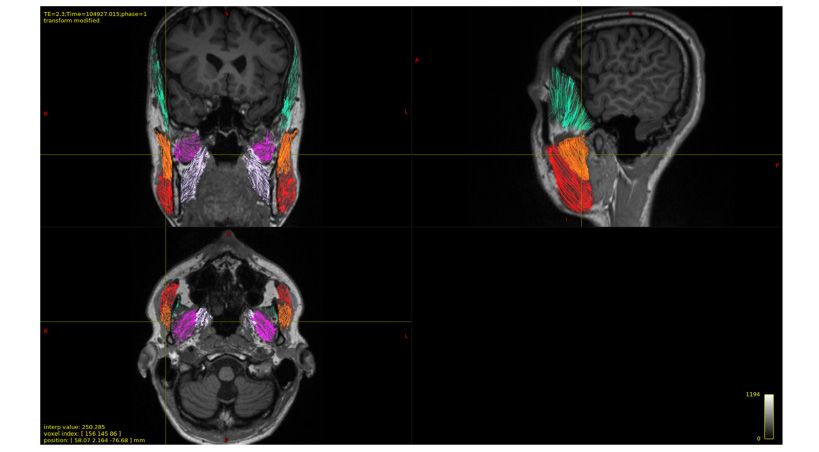

Diseño del estudio: Se obtuvieron imágenes de resonancia magnética (MRI) anatómicas y de imágenes por tensor de difusión (DTI) de la región cefálica de un sujeto masculino sano de 24 años, con la mandíbula estabilizada mediante un MAD personalizado en tres posiciones: posición de mordida habitual (PR=0 mm), protrusión media (PMID=3.5 mm), protrusión máxima (PMAX=7 mm). Se realizó tractografía de líneas de flujo (ST) basada en Desconvolución Esférica (SD). Se dibujaron manualmente máscaras anatómicas para los músculos masetero (superficial/profundo), pterigoideo medial y lateral, y temporal. Se calcularon los ángulos formados por cada fibra muscular detectada proyectada en los planos coronal, sagital y axial, y se analizó su distribución. Además, se determinaron el volumen de la vía aérea y el área mínima de sección transversal (CSAMIN) para cada posición.

Resultados: El método ST capturó la orientación de las fibras de todos los músculos masticatorios. Se observaron variaciones en los ángulos de las fibras musculares y el espacio de la vía aérea en las diferentes posiciones mandibulares. Tanto el volumen de la vía aérea como la CSAMIN aumentaron con el incremento de la protrusión.